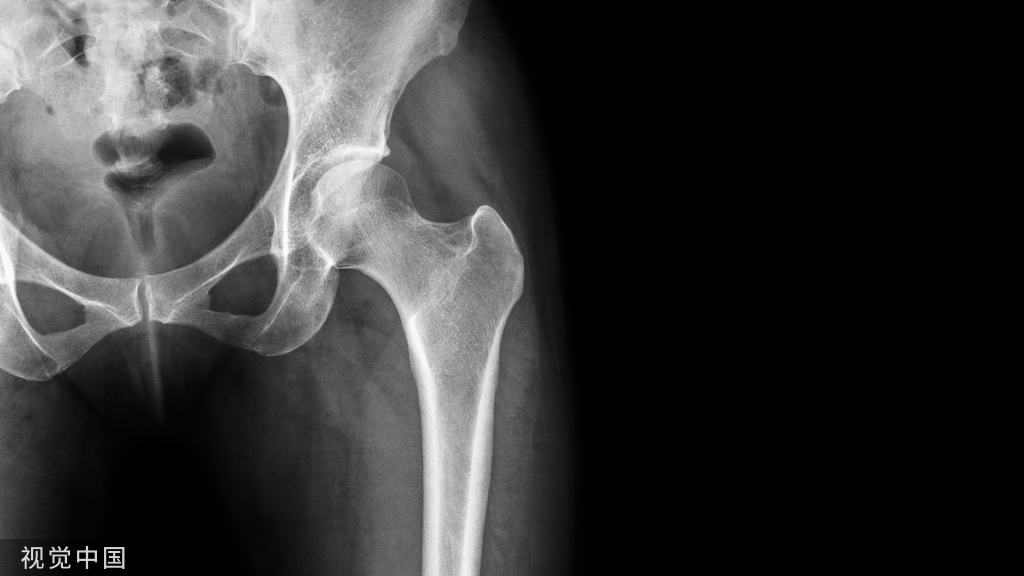

髋关节置换围术期的应用

静脉应用:①单次给药法:髋关节置换术切开皮肤 前5~10 min,氨甲环酸10~50 mg/kg或1~3 g静脉滴注完毕;

②多次给药法:首次给药同单次给药法,术后 24 h内每间隔3~6 h给药1次(每次10 mg/kg或1 g)。

局部应用:髋关节置换术中氨甲环酸 1~3 g 局部 应用

静脉和局部联合应用:静脉方法同单纯静脉应用,联合关闭切口 前氨甲环酸1~2 g局部应用。